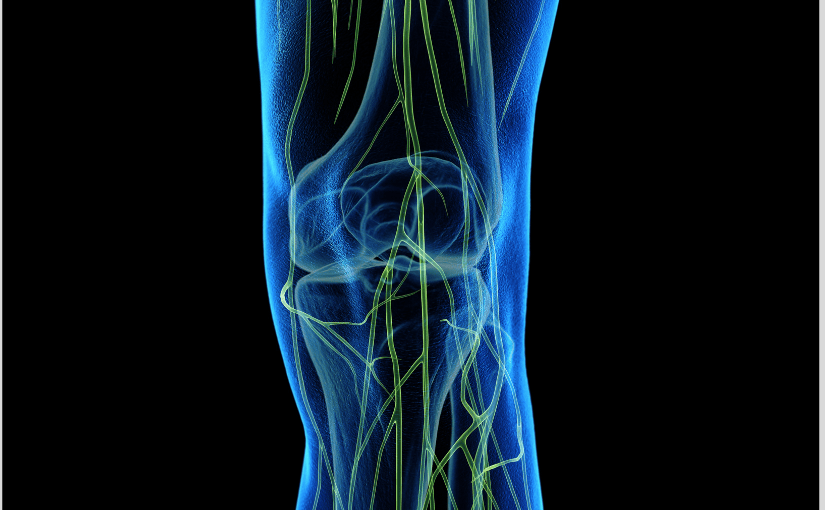

Your ability to walk, stand, and move through daily life relies on the femoral nerve, which is the largest of five nerve branches from your lumbar plexus in the lower spine. You have one femoral nerve on each side of your body that controls hip and knee movement while transmitting sensations of touch, pain, and temperature from your legs to your brain.

This nerve is important for basic activities like walking, standing, and climbing stairs, as it controls thigh muscles and provides sensation to the front and inner thigh, knee, and lower leg areas. When lower spine issues such as misalignments, disc problems, or muscle tension interfere with femoral nerve function, you may experience pain, numbness, tingling, or weakness throughout your leg. Simple tasks can become unexpectedly difficult.This is where chiro therapy comes in. It addresses these problems at their source by restoring proper spinal alignment, reducing nerve interference, and supporting your body’s natural healing processes—helping you regain comfortable, confident movement.

The femoral nerve is a principal orchestrator of lower limb movement and sensation. Its comprehensive innervation patterns underscore its critical role in daily mobility and proprioception. They are elaborated in the succeeding paragraphs.

The nerve controls the big muscles that flex the hip, including the iliacus, pectineus, and sartorius, which are necessary for bending the hip. It also supplies all four heads of the quadriceps femoris muscle—the rectus femoris, vastus medialis, vastus intermedius, and vastus lateralis—the main extensors of the knee. A weakness in the iliopsoas muscle, for example, can cause significant difficulty in hip flexion and impede activities like climbing stairs.

Beyond helping you move, the femoral nerve also plays a key role in how you feel sensations in your leg. The nerve splits into different branches that provide feeling to various areas of your lower body.

One part of the nerve creates smaller nerves that give sensation to the skin on the front and inner parts of your thigh. Another part becomes the saphenous nerve, which is the largest sensory branch of the femoral nerve. This nerve provides feeling to the skin along the inner side of your leg, extending down to the inner part of your foot and even reaching your big toe.

This means when your femoral nerve is working properly, you can feel touch, pressure, and temperature changes throughout these areas of your leg and foot.

The femoral nerve also innervates the hip and knee joints and provides proprioceptive feedback—the body’s sense of its position and movement in space. Notably, the nerve to the vastus medialis muscle has a high density of proprioceptive fibers from the knee joint and is therefore thicker. The femoral nerve is also part of the patellar tendon reflex, a common clinical test to assess the function of the L3-L4 spinal nerve roots.